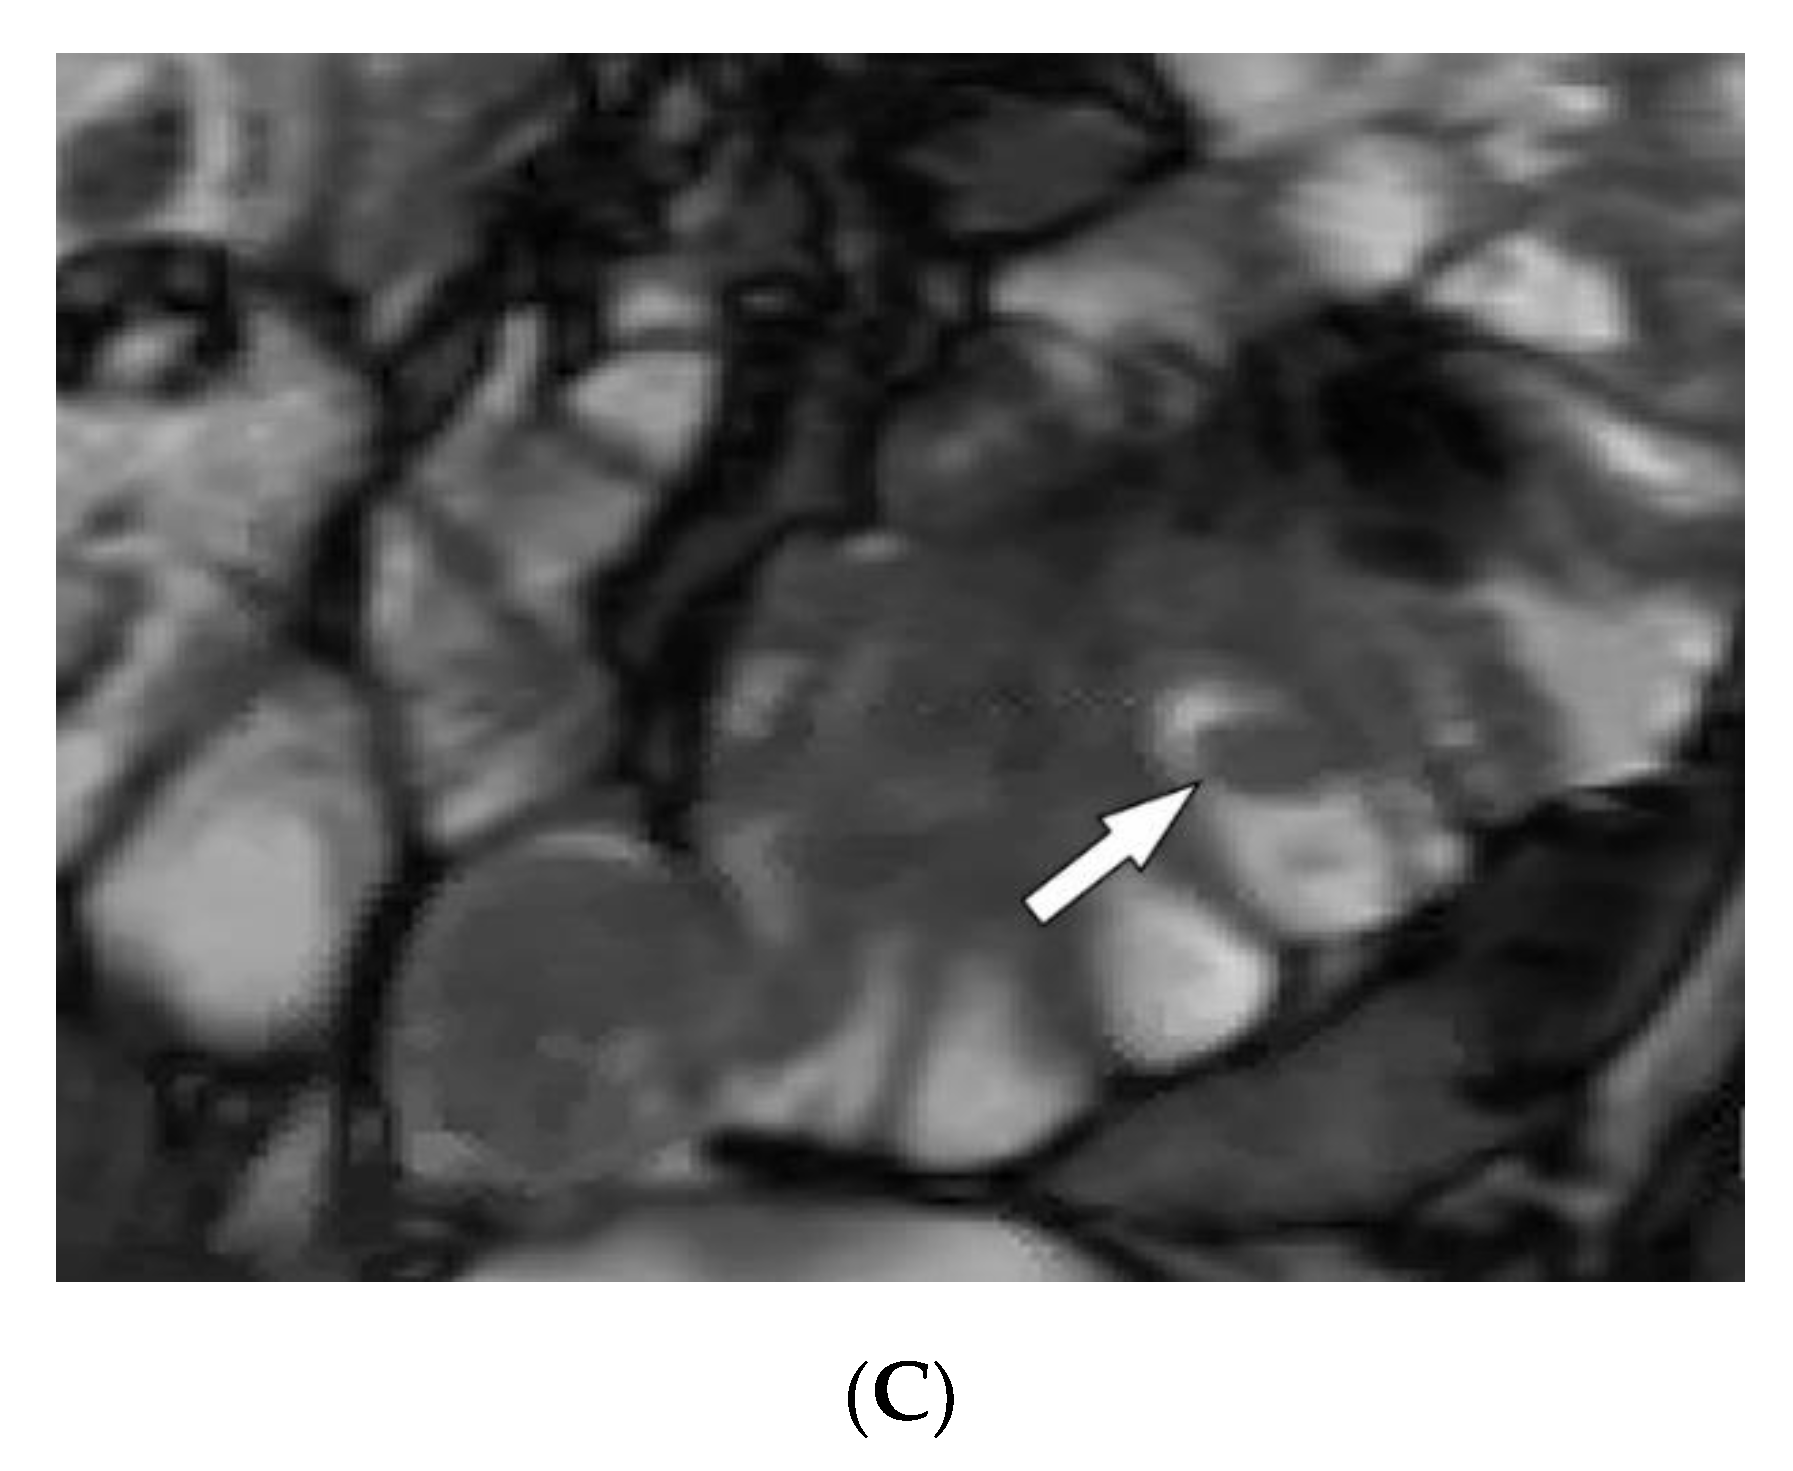

4.2. Kaposi Sarcoma

| Kaposi sarcoma | Erythematous or violaceous macules, plaques, nodules Pulmonary involvement Gastrointestinal involvement | Nodular enhancing masses Peribroncovascular nodules and halo sign |